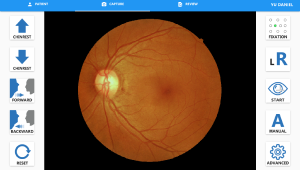

Високоякісне зображення сітківки

Завдяки високій роздільній здатності 12 мільйонів пікселів NFC-700 надає діагностиці сітківки ока та системам AI більш точну та корисну інформацію, що підвищує точність та ефективність діагностики.

NFC-700 надає фільтри без червоного, негативу плівки, RGB, градації сірого, щоб користувачі могли змінювати або застосовувати фотоефекти до зображення для різних цілей.